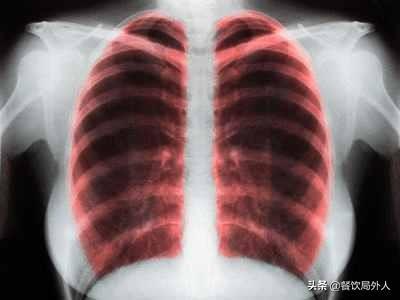

结核病一直以来都是众所周知的可怕疾病。仅在二十世纪初就造成了约1亿人死亡,虽然随着人类医疗科技的飞速发展,肺结核的致死率稍有好转。可是,每年仍有大约150万人死于肺结核。肺结核的并发症会导致身体虚弱,机体免疫力减弱,抵抗疾病能力下降,从而导致的慢性心肺功能不全、全身衰竭、等是致死率居高不下的主要原因。

疾病来源:

肺结核是由结核分支杆菌引起的,它属于细菌不属于病毒。

传播方式:

空气传播,唾液等液体均可以传播。